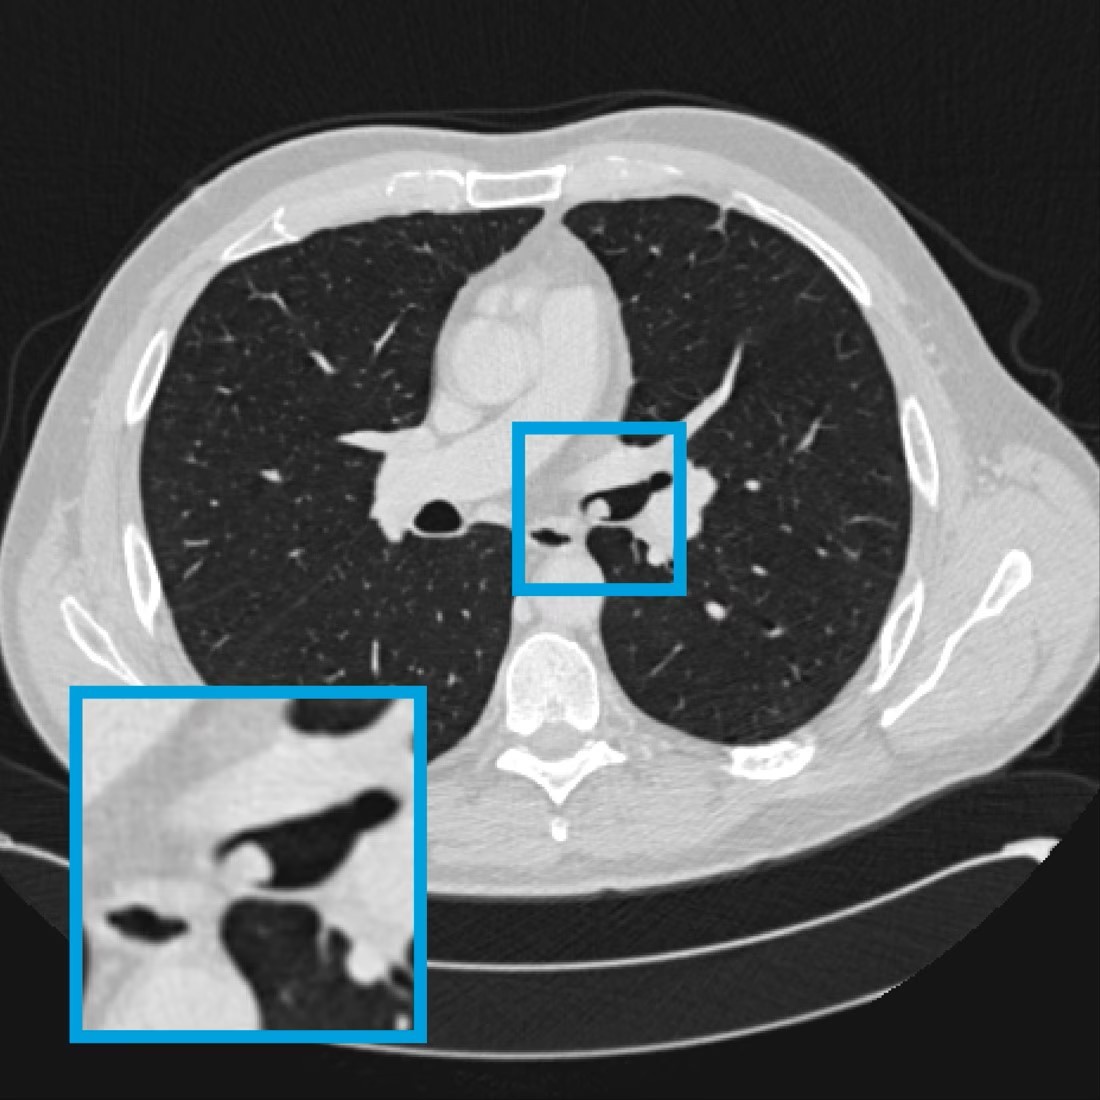

This deep-learning model detects airway nodules on thoracic or thoracoabdominal CT examinations acquired in routine clinical practice. It is developed on a dataset of 320 CT annotated clinical scans, consisting of 160 scans containing airway nodules and 160 scans without airway nodules.